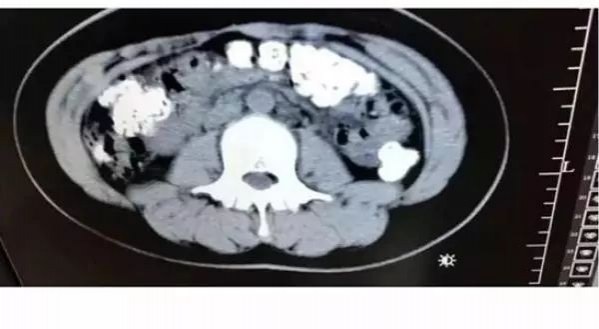

ขณะที่ก่อนหน้านี้ยังมีรายงานข่าวจากประเทศจีน ที่เผยแผร่ผ่านเว็บไซต์โพสต์ทูเดย์ พบ เม็ดไข่มุกจากประเทศจีนทำส่วนวัตถุดิบกินไม่ได้ อย่างยางรถยนต์และหนังรองเท้า หลังพบผู้ดื่มชานมไข่มุกรายหนึ่งทำซีดีสแกนช่องท้องแล้วพบวัสดุเป็นเม็ดสีขาวคล้ายไข่มุกตกค้างอยู่จำนวนหนึ่ง ซึ่งตามปกติแล้ว เม็ดไข่มุกที่ทำจากแป้งธรรมชาติ ร่างกายสามารถย่อยสลายและขับถ่ายออกมาได้โดยไม่เหลือส่วนตกค้าง